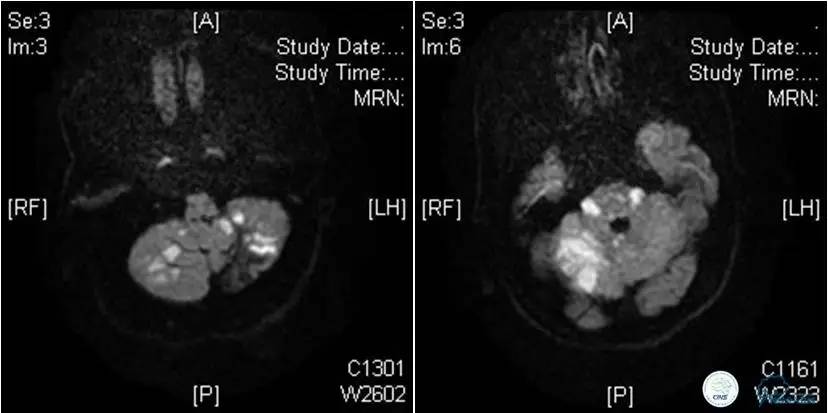

患者:49岁男性,左侧偏瘫1个月,药物治疗、康复训练效果不好,转我院,肌力0~1级。

core-clilnical明显不匹配,是介入开通的合适患者。